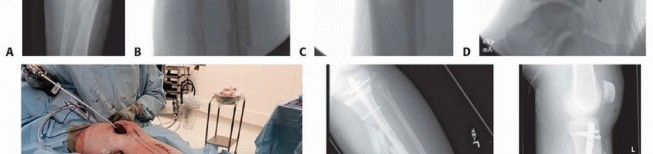

### FIG 1 • A. The metaphyseal segment extends with knee flexion secondary to the pull of the patellar tendon. B. The anterior tibial crest is palpable and represents the vertical lateral border of the tibia. Palpation of the crest can help aid in starting wire orientation. C. Anterior neurovascular structures are at risk during anterior placement of distal interlocking bolts; internal rotation may decrease the risk of arterial injury. A detailed neurovascular examination is critical to avoid the devastating complications associated with compartment syndrome, which can occur in both closed and open fractures (see Cha 53). ## IMAGING AND OTHER DIAGNOSTIC STUDIES Full-length anteroposterior (AP) and lateral plain radiographs are necessary to adequately evaluate the tibia and fibula. Complete orthogonal views of the tibia and fibula help evaluate for concurrent fractures or dislocation and any preexisting deformity or implants. Orthogonal radiographic views of the knee and ankle are required to rule out articular involvement. Axial computed tomography (CT) scan can be used for proximal and distal fractures to rule out intra-articular fracture extension. Nondisplaced fracture lines are common. Gunshot wounds may merit CT evaluation to rule out intra-articular bullet fragments and intra-articular fracture extension. Magnetic resonance imaging (MRI) is not useful for most diaphyseal or metadiaphyseal fractures. Ankle-brachial index (systolic pressure in injured leg below injury divided by systolic pressure of the brachium) after fracture reduction should be used to rule out vascular injuries in severely displaced fractures or fractures with severe soft tissue injury. Values of less than 0.9 may be indicative of vascular injury, requiring further investigation. 18 549 Compartment pressure evaluation with a commercially available handheld single-stick monitor or with a sideported catheter connected to a pressure monitor (using the arterial line setup) is indicated in patients who have severe or increasing swelling and are not able to comply with physical examination and questioning. Observe for early signs of compartment syndrome in all patients with tibial diaphyseal fractures. Open fracture does not preclude development of compartment syndrome. Measure the pressure difference between the diastolic pressure and the intracompartmental pressure—a differential value of less than 30 mm Hg is considered an indication for a four-compartment fasciotomy. 17 ## NONOPERATIVE MANAGEMENT Nonoperative management is indicated in ambulatory patients for closed and open fractures that do not require flap coverage and that do not present with excessive initial shortening or unacceptable angulation when a cast is applied ( FIG 2). An intact fibula with an axially unstable fracture pattern (ie, short oblique, butterfly fragment, or comminuted) is at risk for shortening and varus deformities and is a relative contraindication to nonoperative management. A higher rate of malunion and nonunion with nonoperative management is seen in higher energy fractures. 2, 9 Joint stiffness, especially hindfoot, is common with all forms of prolonged immobilization. 7, 22 Initial treatment includes ˜2 weeks of a long-leg splint, then a long-leg cast for 2 to 4 weeks. When the initial swelling has subsided, the patient is graduated to a patellar tendon or functional brace. Weight bearing is allowed and encouraged.

### FIG 2 • A-C. An oblique diaphyseal tibial shaft fracture treated nonoperatively to union. (Courtesy of Paul Tornetta III, MD.) Radiographs are evaluated at 1- to 2-week intervals over the first month of treatment to confirm maintenance of acceptable alignment. ## SURGICAL MANAGEMENT